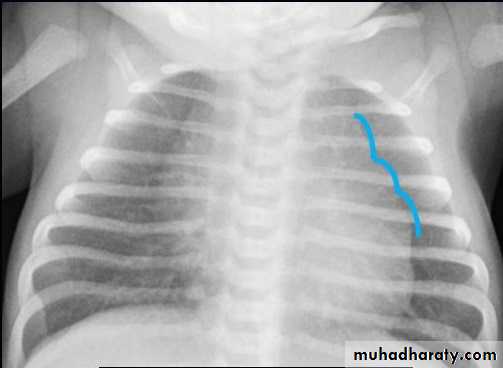

CXR of a neonate ,PA view shows thymus gland (normal finding not a disease ) with indentationsUL: Thymus Indentation sign. UR: Thymic wave sign, Lower: Thymic Sail sign

normal chest XR of the infant( normal thymus gland) Sail sign